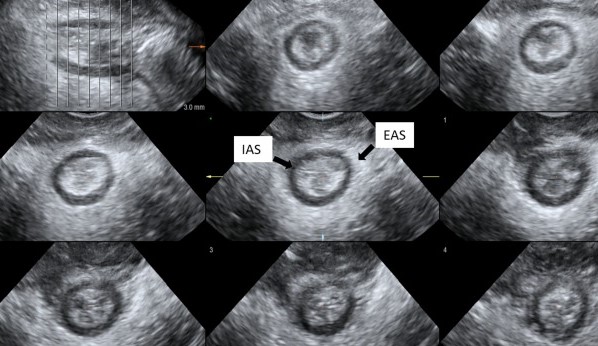

Επικαλυπτική σφιγκτηροπλαστική. Σχηματική απεικόνιση (Ευγενική παραχώρηση Dr. V. Penopoulos)

Πράσινο βέλος - εσωτερικός και κίτρινο βέλος - εξωτερικός σφιγκτήρας μετά επιμελή αποκόλληση (Ευγενική παραχώρηση Dr. V. Penopoulos)